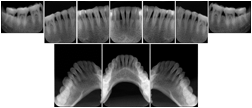

Intra-oral radiography typically involves acquisition of multiple images of various parts of the dentition. Many digital radiographic systems offer customized templates that are used for displaying the images in a study on the screen. These templates may also be referred to as mounts or view sets. The Structured Display Object represents a standard method of encoding and exchanging the layout and intended display of Structured Displays. A structured display object created in this manner could be stored with a study and exchanged with images to allow for complete reproduction of the original exam.

In most standard cases, images are oriented in structured layouts. These structured displays are useful to be shared between providers for reference purposes.